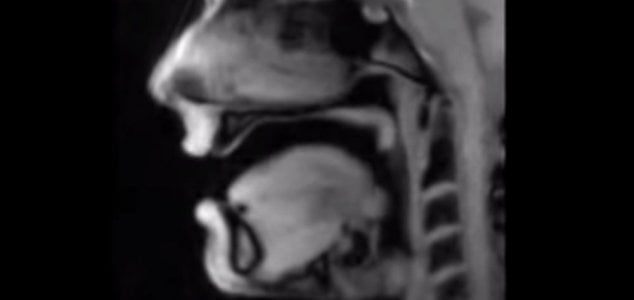

Vídeo de ressonância magnética mostra o que acontece quando você fala

Um novo vídeo notável mostra como é o interior da sua boca…